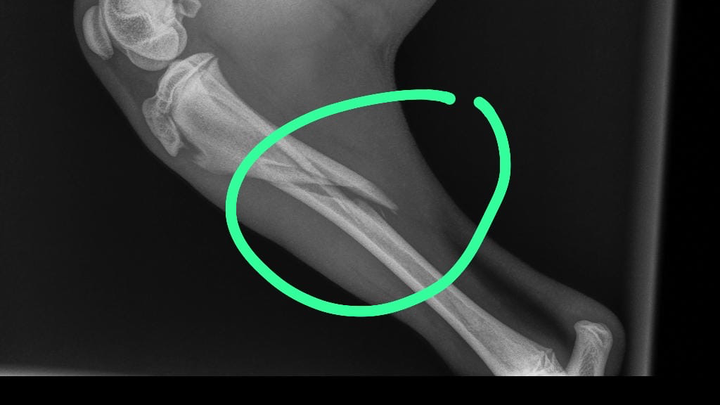

Mijn naam is percy zit in groot probleem mijn lieve hond puppy Bintang heeft ze pootje gebroken en is hoge kosten gekomen hoop dat ik hier mensen zijn die me kunnen helpen